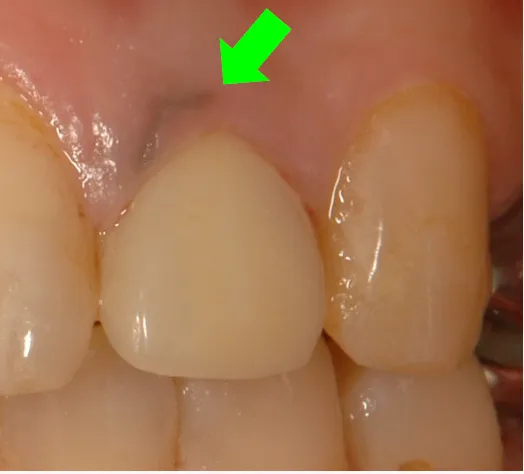

①根が黒い

虫歯が大きく中の神経を抜いてしまった際の治療で差し歯(被せ物)を入れることがあります。この差し歯や中に使用される土台が劣化しやすい金属だと、後に腐食することで、溶け出した金属イオンが根に沈着し黒くなります。

より目立ちやすい前歯などの根が黒くなると、重大な審美障害となる事が多々あります。

被せ物を外すと根が真っ黒に変色しています。

古い銀合金の土台が使用されていました。これが錆びて、

金属イオンが根に染み付いて変色していました。

残念ながら根に染み付いた金属イオンは完全には取れません。

●銀合金の土台を外して、樹脂製ファイバーの土台に変更

●歯の強度を失わないように、可能な限り変色部を取り除く

●歯茎のきわは歯茎の厚みが薄く、根の色を透過してしまうので、なるべく根の方までセラミックでカバーする

このような治療を行うことで、歯茎の黒ずみはほとんどわからなくなり、被せ物もセラミックで作り直すことで、患者様のご希望通りの自然な見た目を実現することができました。